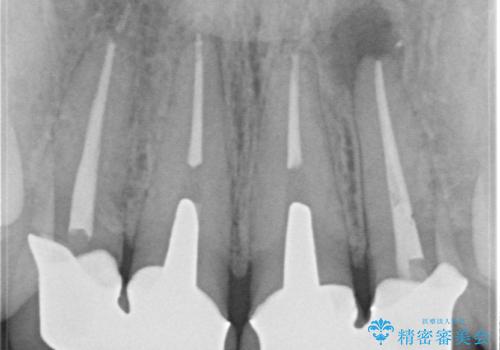

[ 精密根管治療 ] 他院で抜歯しかないと言われた歯を残す